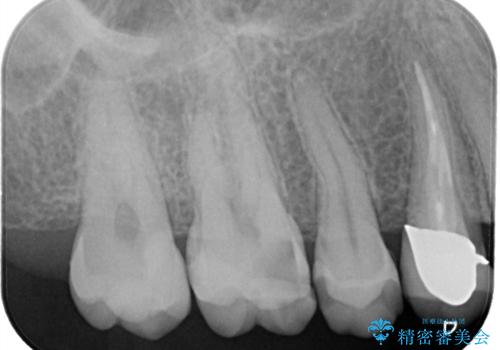

- 虫歯が大きく神経まで達していたので、VPT(歯髄温存療法)を行って細菌感染した部分の神経のみ取り除き、保存可能な神経は保存し被せ物はセラミックインレーで治療を行いました。

昔の歯科医療では神経まで虫歯が達している場合は神経を全て取らなければいけませんでした。しかし現代の歯科医療ではBio-C SealerやMTAセメントの開発により健康な神経を残せるようになりました。

※術前に神経の状態の検査を行い、術中にもマイクロスコープにて神経の状態を直接確認したうえで残せると判断した場合に行っています。